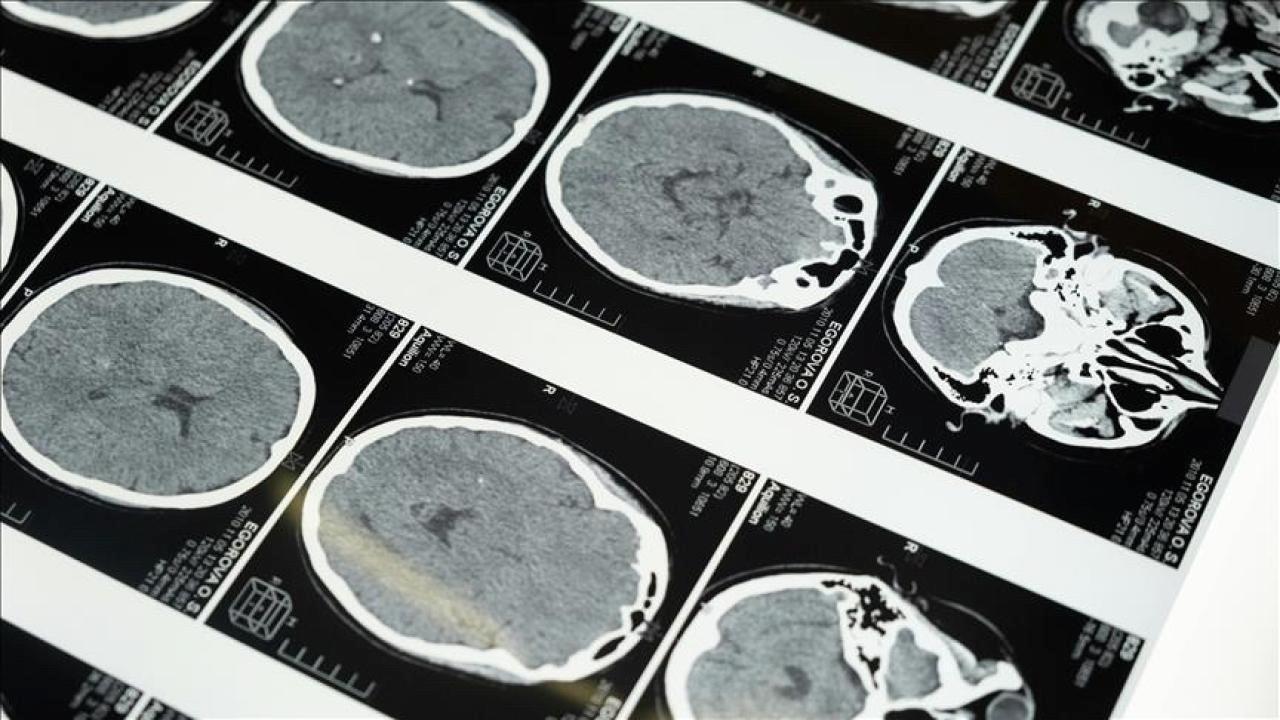

İstanbul’da düzenlenen 1. Dünya Girişimsel Nöroloji ve Nöroşirürji Kongresi’nin (WINNC 2025) düzenleme komitesinde yer alan Eskişehir Osmangazi Üniversitesi Tıp Fakültesi Nöroloji Ana Bilim Kolu Öğretim Üyesi ve İnme Merkezi Sorumlusu Prof. Dr. Atilla Özcan Özdemir, inmenin beyin damarlarının tıkanması (iskemik) ve beyin kanaması halinde gelişen iki tipinin olduğunu söyledi.

“Özellikle pıhtıyla tıkanan beyin damarının açılmasıyla ilgili stratejiler gelişti. İnmede erken periyotta yapılan damar açma tedavileri konusunda ülke olarak düzgün durumdayız. İnme tedavisinde pıhtıyla tıkalı beyin damarının anjiyo yoluyla açılması mümkün. Böylece hastanın 3 ay sonra, 1 yıl sonra kendi işini yapabilecek hale getirilmesi sağlanabiliyor. İnme merkezlerinde uygulanabilen bu süreci birinci 24 saat içerisinde belli hasta kümelerine yapabiliyoruz. Birinci 24 saat çok kritik, bu müdahaleler de yalnızca inme merkezlerinde yapılabiliyor.”